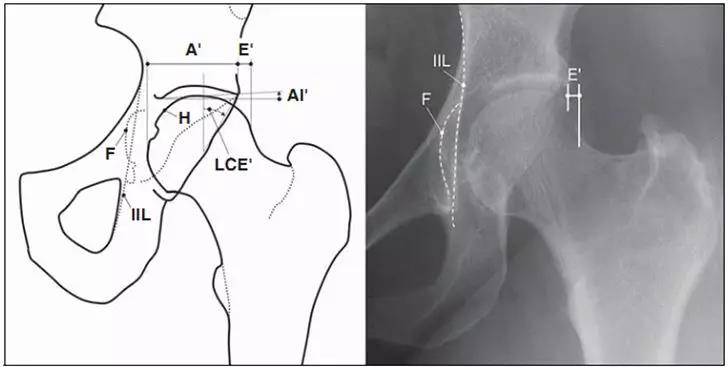

- 髋臼突出:更内侧(成人:男性>3mm,女性>6mm;儿童:男性>1mm,女性>3mm。)

- 髋臼前突,股骨头与髂坐线相交